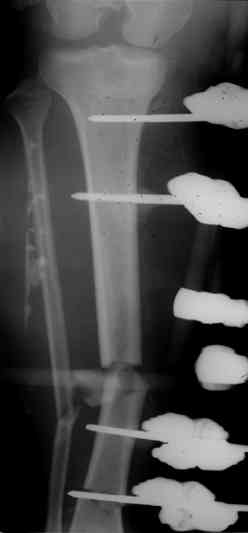

Коллеги! Прошу совета, какую тактику избрать при лечении.Больной 27 лет, мотоциклист. Поступил 23.04.10 ДЗ. О. перелом н.з левого бедра Gustillo 3b (c повреждение бедренной вены), О.Правого бедра Gustillo 2, з. фрагментарный перелом левой голени.При поступлении Hb 66 ISS 40, Фиксация стержневыми аппратами, сосудистые хирурги выполнили шов вены. Выполена резекция бедренной кости 9 см. На 7 сутки Желудочно-кмшечное кроветечение из стрессовых язв, 12 сутки флотирующий тромтоз 14 см установлен кава-фильтр. На 15 сутки закрытие ран местными тканями. Раны заживают первично. Воспаления на стержнях нет. В настоящий момент планируем. Переход со стержневых аппаратов на стержни с антибактериальным покрытием на правом бедре и левой голени. Левое бедро планируем продолжить фиксировать в стержневом аппарате.

Вопрос: что делать с левым бедром? Учитывая внутрисутавной характер перелома, дефект бедра 9 см.